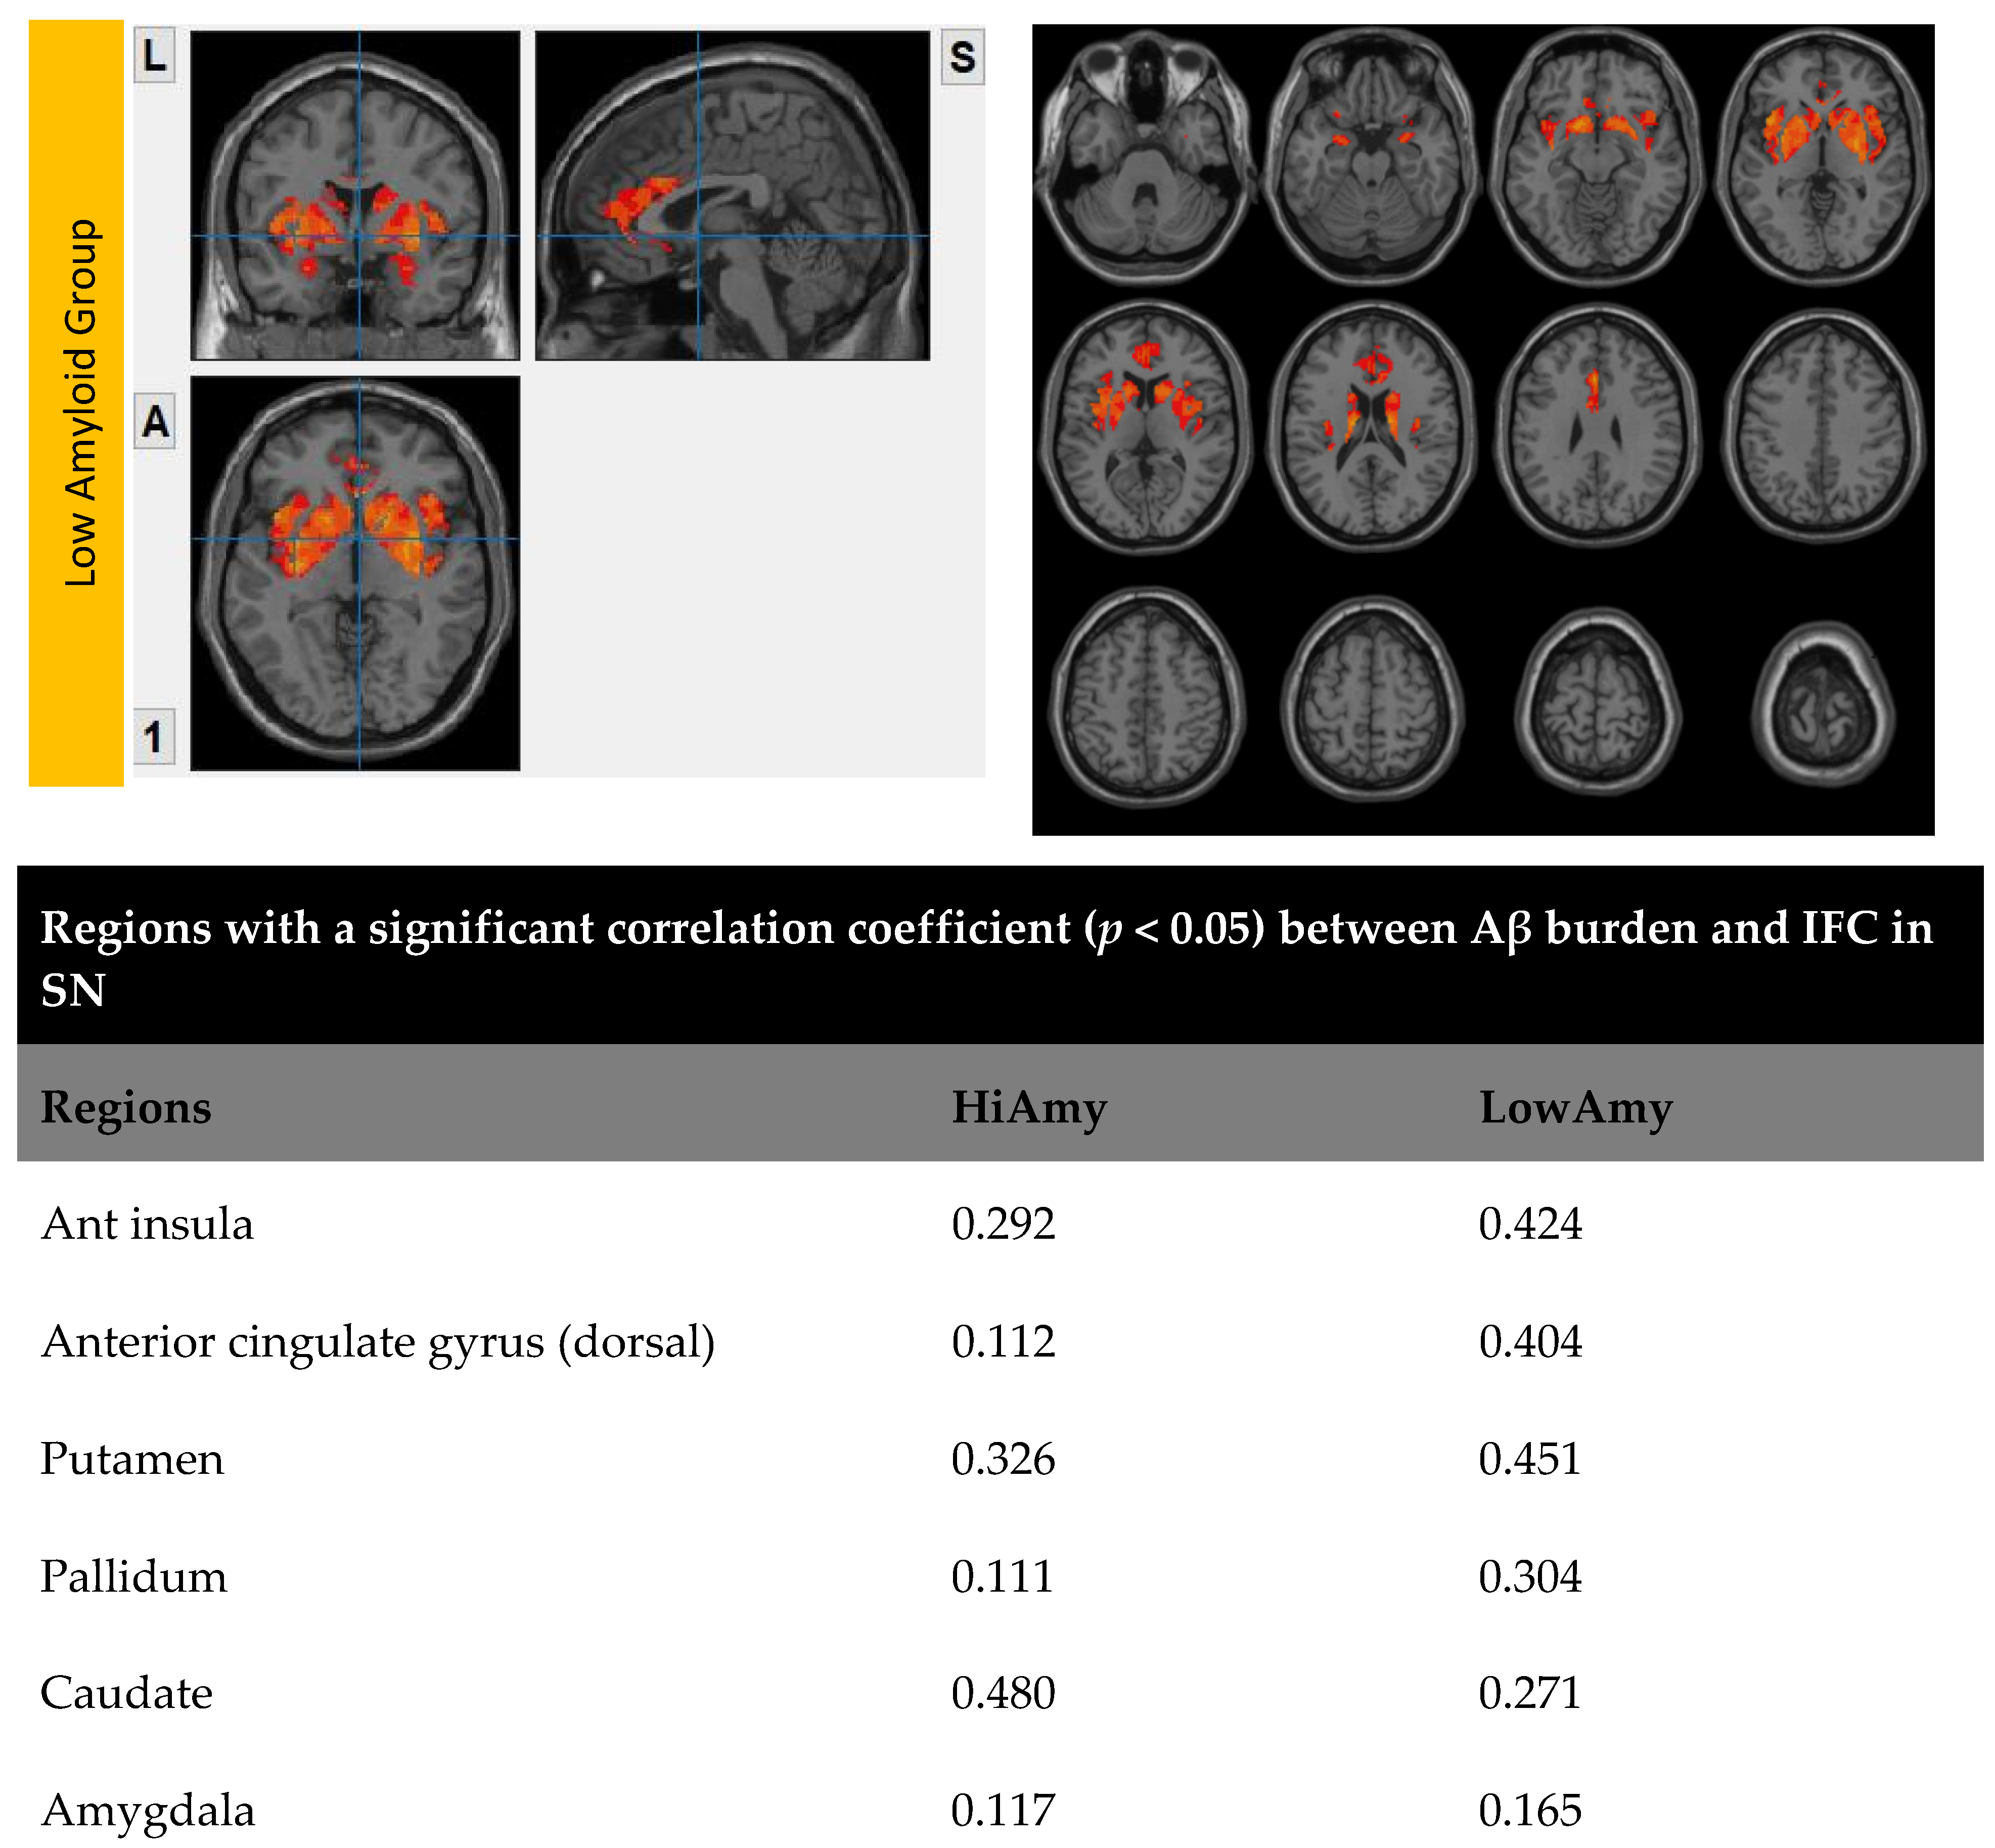

7.3. Within SN